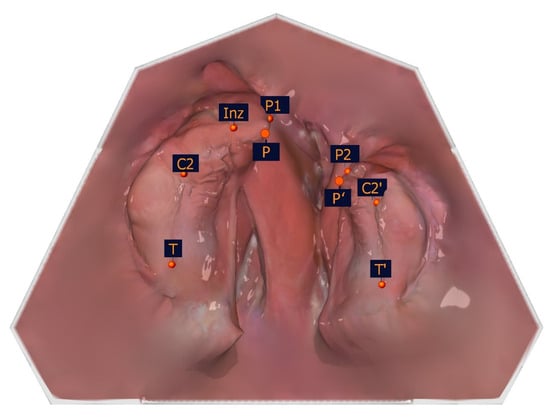

To identify the transversal landmarks, the large and small segments were divided into the subsegments (T-C2, C2-Inz, and Inz-P1 for the large segment and P2-C2′ and C2′-T′ for the small segment). The most vestibular and most palatal points in each section were determined (Table 2, Figure 5).

Figure 5. Illustration of the segmental width measuring measurement points of the partial jaw segments. The segmental width measurement points and their description are presented in Table 2.